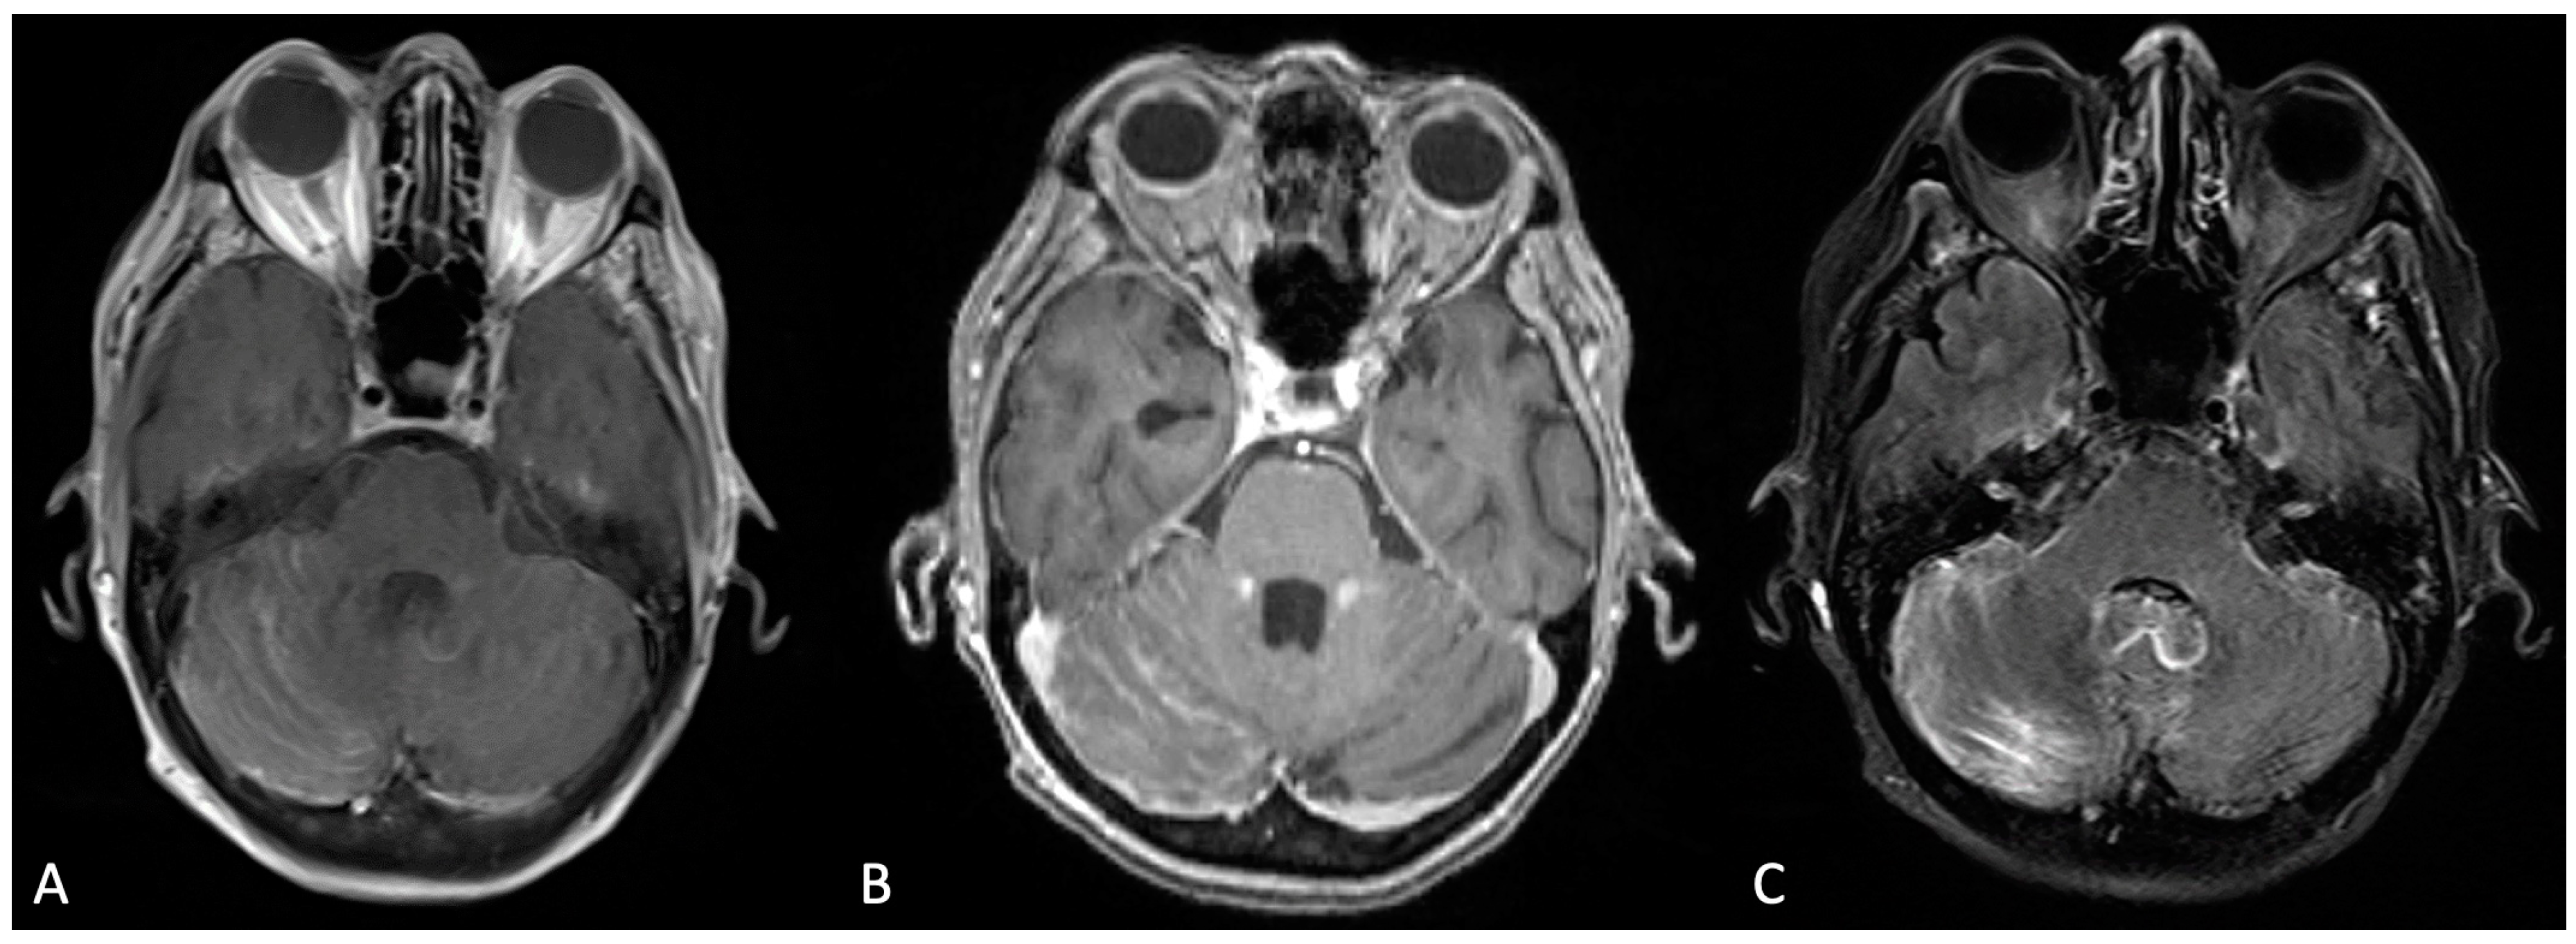

On the matter of modality-based diagnosis, the gold standard comprises two modalities in the form of imaging and cytological analyses. T1-weighted magnetic resonance imaging (MRI) with gadolinium contrast is the imaging tool of choice. The observational patterns to hearken to include various morphologic enhancements of the cranial nerve, or linear/curvilinear enhancements, and nodular aberrancies [2,7]. These are often noted in select areas, such as the cerebral convexities, basal cisterns, and ventricular ependyma [4]. Figure 1 depicts an MRI scan of leptomeningeal involvement following breast cancer metastases. Within the spine, particularly in the cauda equina region, similar observations should raise suspicion for LMD [4]. Preliminary MRI is becoming an increasingly routine measure for early brain metastasis. As such, several structure densities along the brainstem, cranial nerves, meninges, and ventricles have been correlated with leptomeningeal metastasis. Of note, some findings, such as increased ventricle MRI density, can be a consequence of LMD-associated disorders, in this case hydrocephalus. Since negative MRI findings are not exclusionary, the second modality, CSF cytology, is an essential layer in the diagnosis of this pathology. Conventional cytology hinges on the presence of malignant cells, irrespective of their primary origin, as determined by a cytopathologist. However, cancer specific markers may aid in the determination of the origin, such as the presence of VEGF. In general, the sensitivity and specificity of LMD diagnosis following CSF cytology range from 50–60% and 75–80%, respectively, upon first and second aspirations of CSF [1,3]. Therefore, it is highly encouraged to conduct a second analysis of the CSF when possible, in order to increase the diagnostic capacity for LMD. As a soft requirement, a minimum of 10 CSF mL should be collected for sufficient analysis, with some studies reporting a minimum of 5–10 mL [1,3]. Additionally, it is recommended that the suspected region of affliction (based on several parameters, such as clinical presentation and imaging) be the area of aspiration; in cases where this is not feasible, the lumbar or cisternal regions should be considered as immediate alternatives [1]. The select biomarkers that are measured to supplement ruling in LMD include pleocytosis, hypoglycorrhachia, and hyperproteinorrachia (elevated CSF protein levels). These findings have been observed with a sensitivity of 50–70% [8]. More novel forms of investigation have arisen in the form of tumor-specific antigens, such as carcinoembryonic antigen (CEA) and alpha-fetoprotein. The latest of these endeavors has manifested itself by relying on cell-free DNA as a source of direction [3]. The sensitivity of this latter technique has been nascently explored, though its sensitivity has been reported at 94% with a specificity of 100% [9]. Indeed, in a recent meta-analysis of 668 patients with circulating tumor cells (CTC) and cell-free tumor DNA, sensitivities and specificities were reported at 87.0% and 97.9% (sensitivity, respectively) and 93.8% and 89.0% (specificity, respectively). This has been more robustly assessed in particular cancer-specific LMDs, such as breast cancer [10]. This includes optimization of isolating and purifying circulating tumor-specific DNA and subsequently identifying targetable mutations. Abnormal MRI and CSF findings, as previously mentioned, in the presence of generalized neurological symptoms can be cause for LMD suspicion.

Figure 1.

Bilateral cerebellar folia hyperenhancement, more prominent on the right, was observed in the post-contrast T1-weighted Turbo Spin Echo (TSE) sequence (A); the T1-weighted Multi-Planar Reconstruction (MPR) sequence (B); and the T2-weighted Turbo Inversion Recovery Magnitude Fat Suppressed (TIRM-FS) sequence (C).